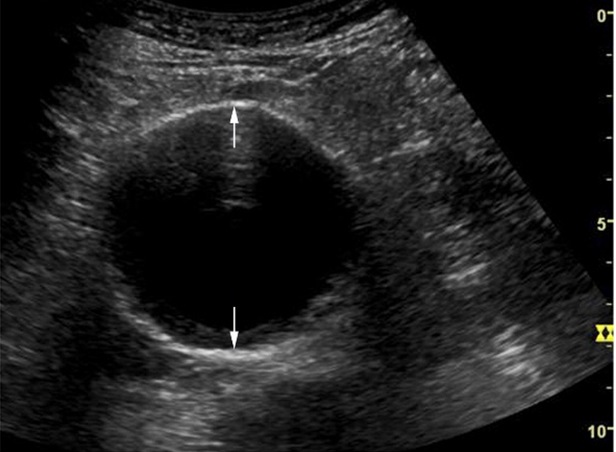

- Siêu âm

Phương pháp này sẽ cho hình ảnh rõ nét và chính xác cấu trúc mạch ở trong bụng, được các bác sĩ sử dụng rất phổ biến.